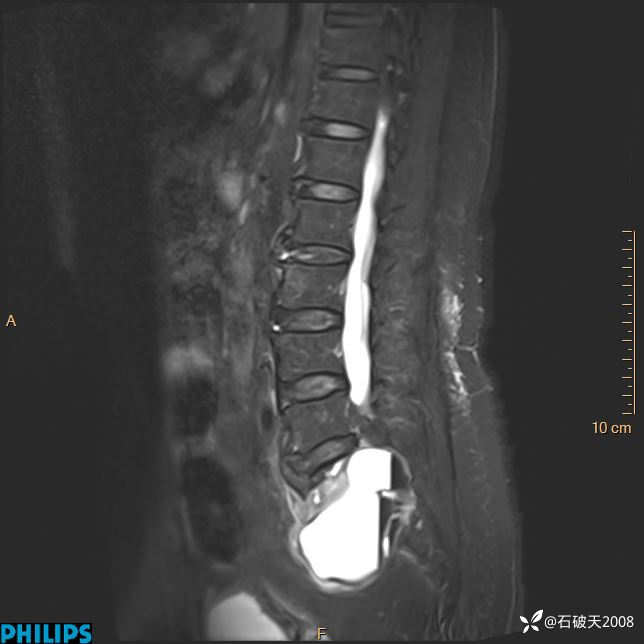

2023年3月份MRI影像

T2矢状位